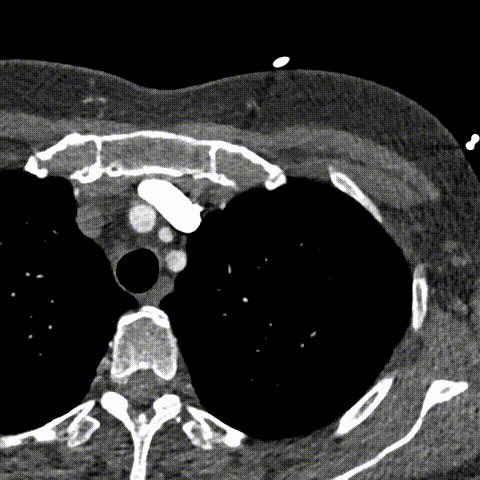

心脏CT证实了这一罕见解剖结构(图C,视频S2;SVC:上腔静脉),显示左右冠状动脉起源正常(红色箭头),分别发自相应冠窦(R:右冠窦,L:左冠窦),未见冠状动脉狭窄。

(图C)心脏CT。红色箭头标记左右冠状动脉开口。缩写:N-无冠瓣,R-右冠瓣,L-左冠瓣,RA-右心房,LA-左心房,RV-右心室,LV-左心室,SVC-上腔静脉,Ao.-升主动脉。